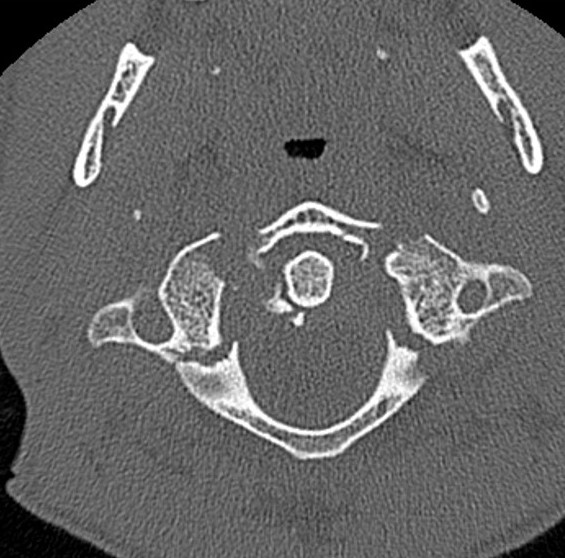

This fracture of C1 is "bursting" with instability?

Jefferson Fracture